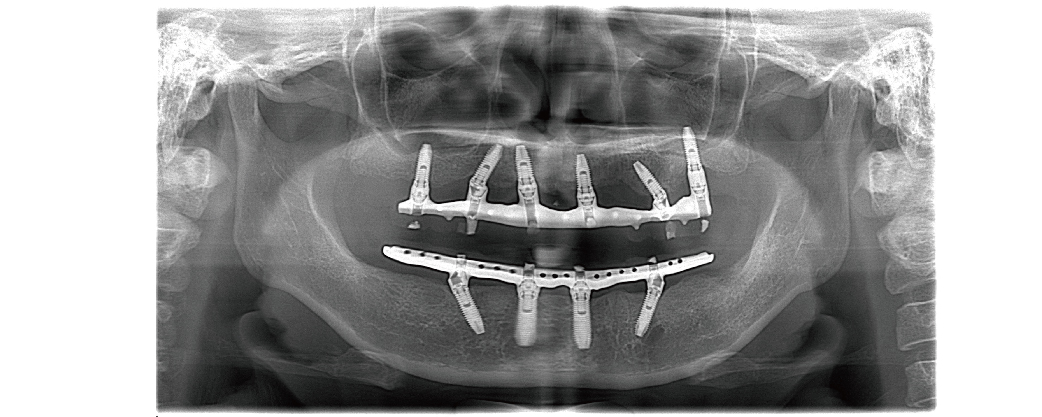

透過四支或六支植體的全口重建治療概念,採用直式和傾斜方式植入植體。後方傾斜植入的植體可以避開下顎的神經線與上顎的鼻竇位置,降低垂直骨量的需求。

不同於一般傳統植牙使用垂直式植體,All-on-4 / 6 一日全口重採用傾斜式植體,所需牙骨量較少,特別適合骨質流失嚴重的病人使用。

對於全口無牙或拔牙數量超過10到12顆的病患,只需從上、下顎黃金三角,也就是一般人牙骨量最高的區域中,選擇四支牙根強化補骨,就能安裝整付固定式假牙,大幅縮短等待補骨癒合的時間。